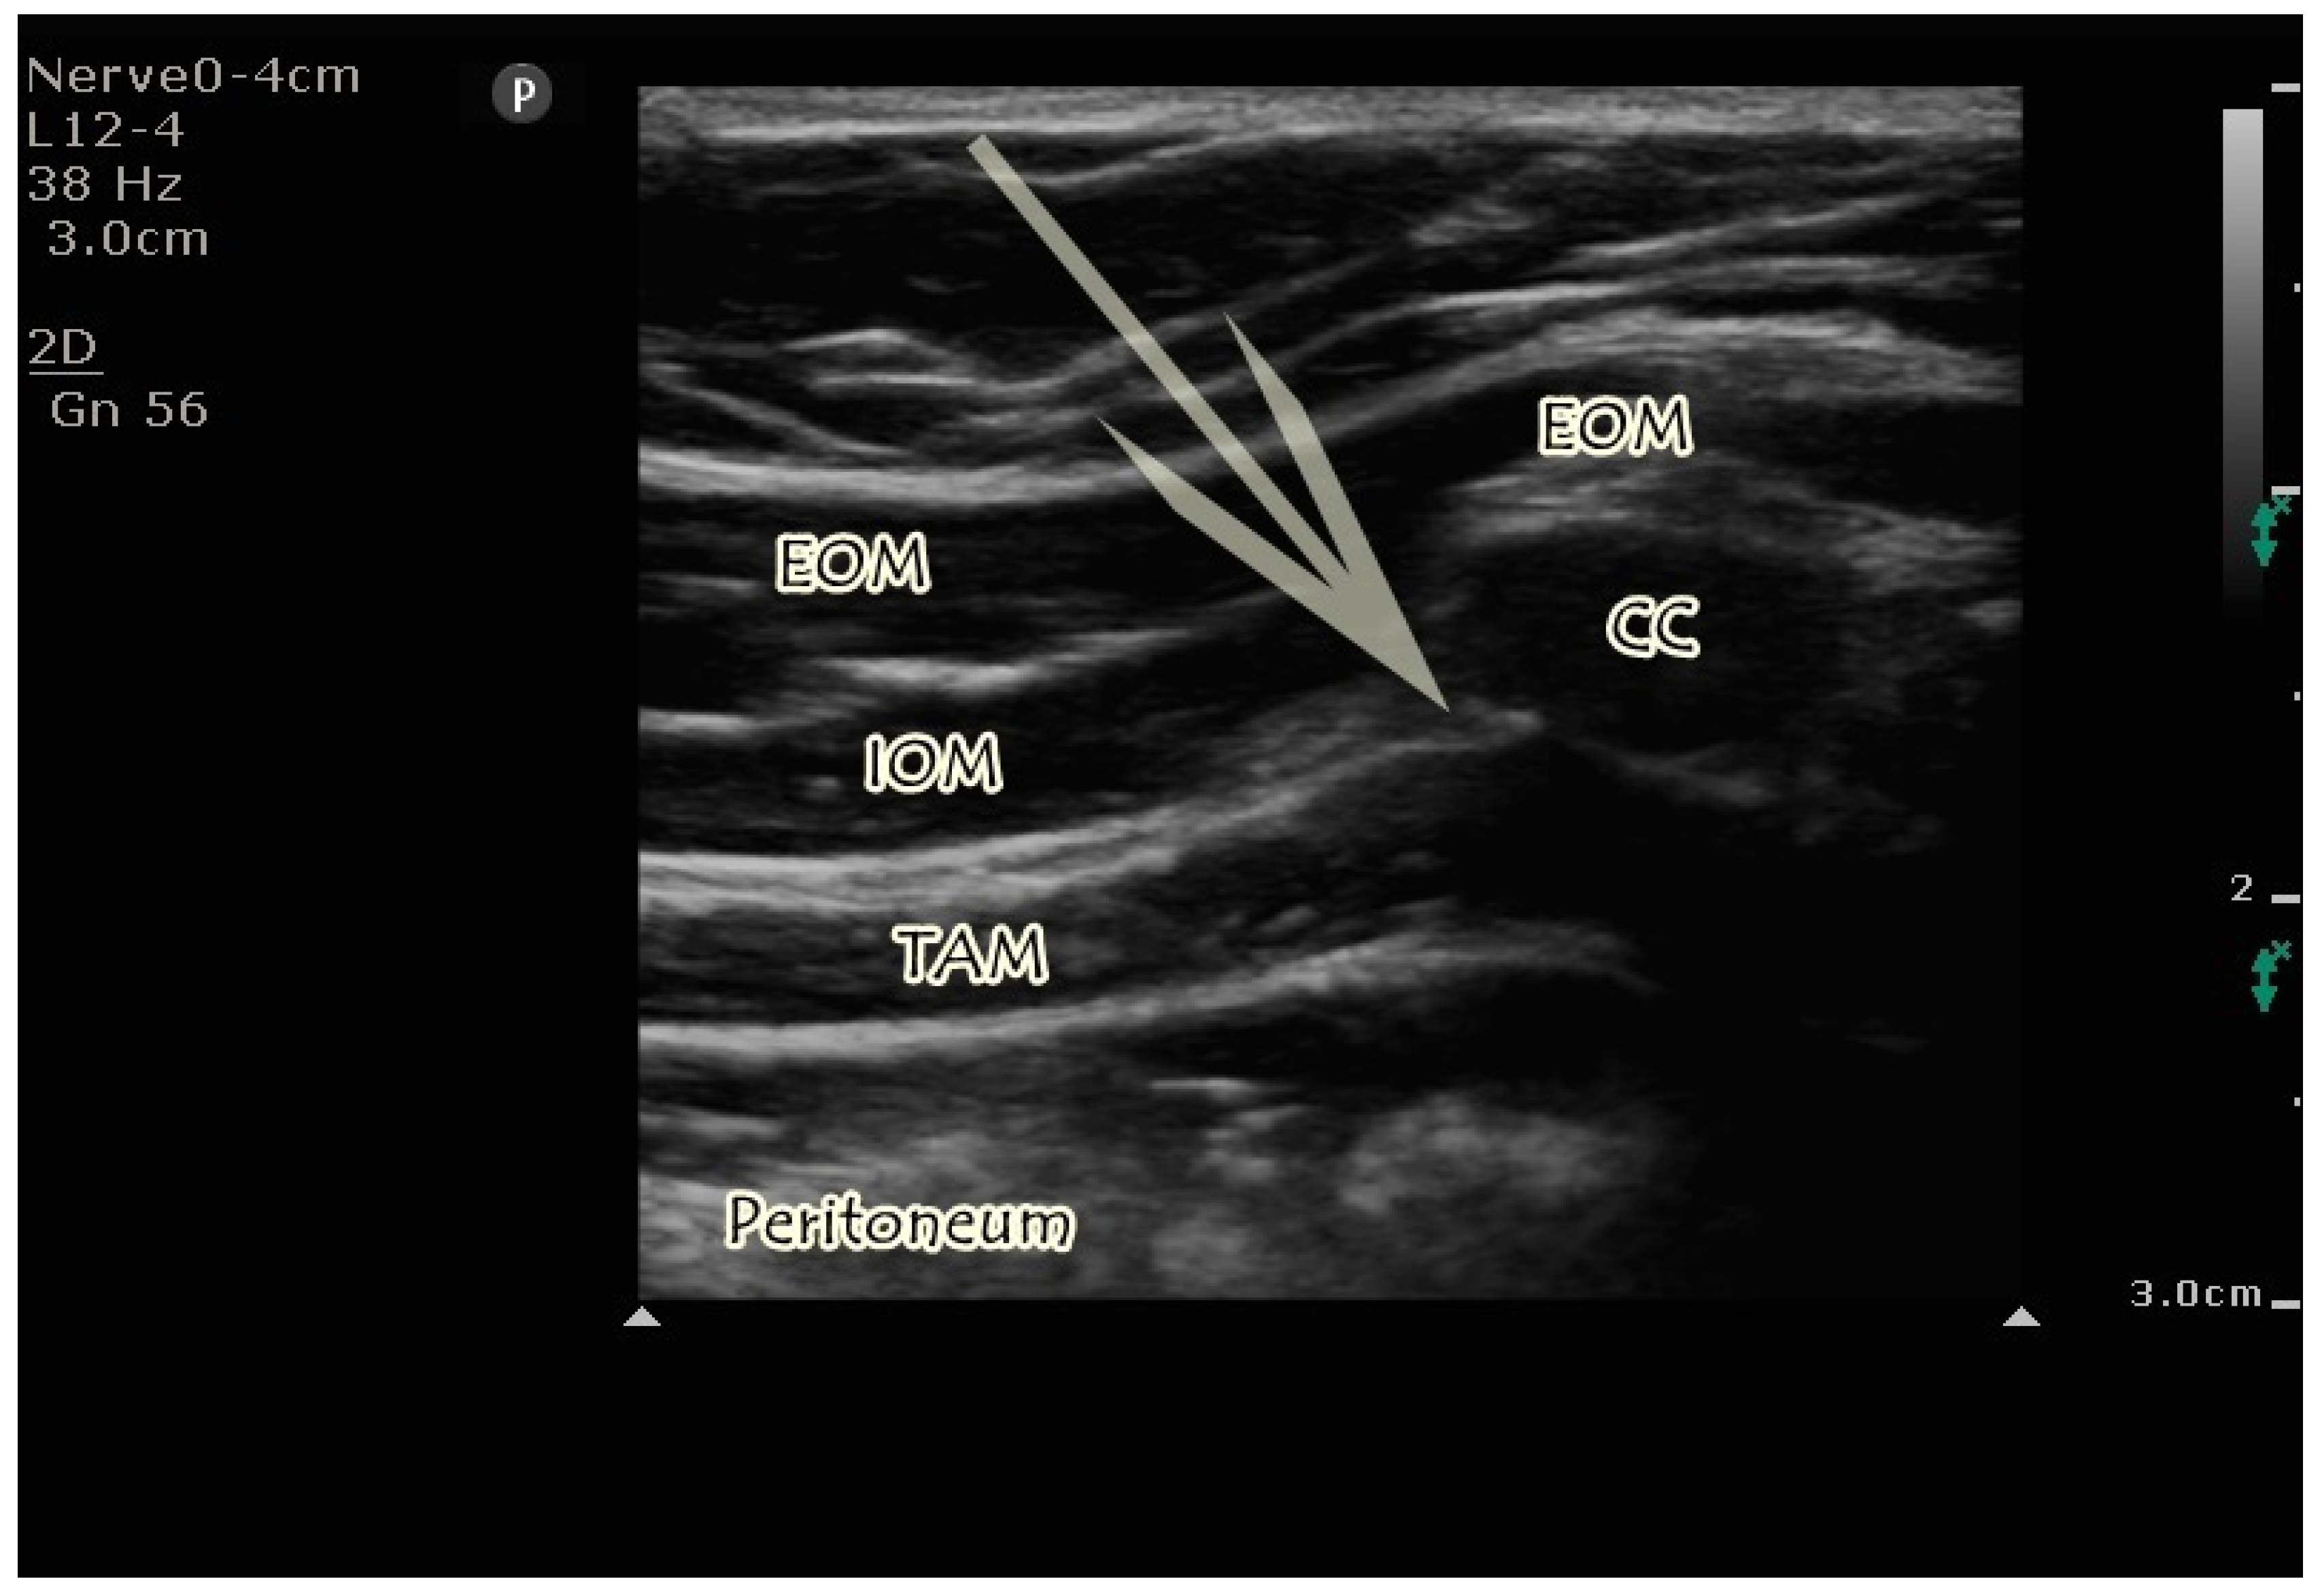

2.4.1. US-Guided M-TAPA Block